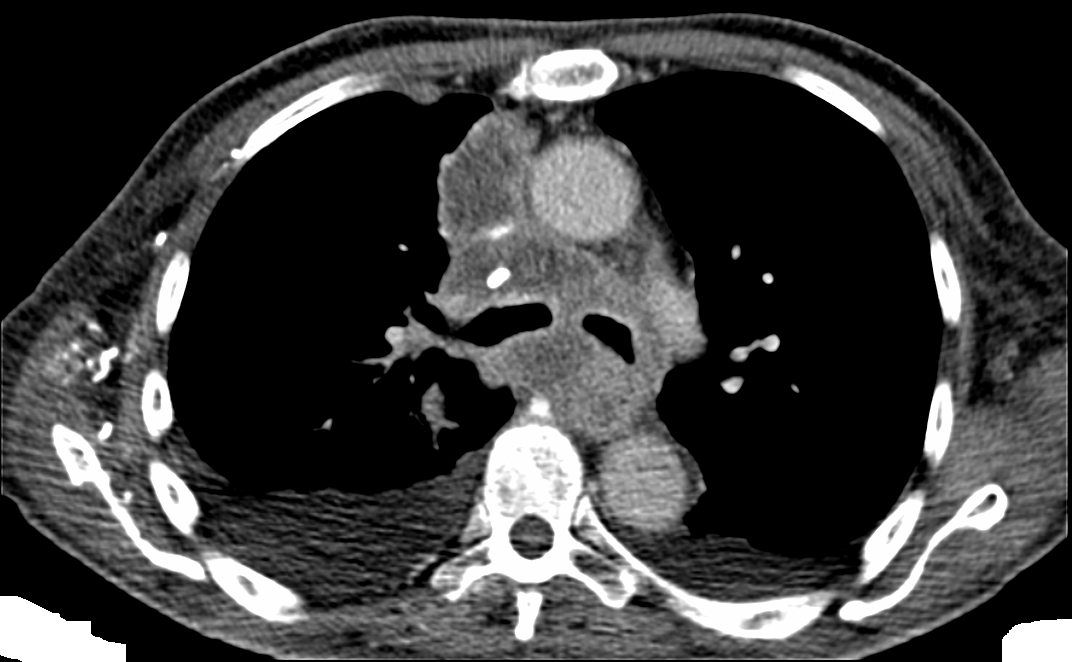

Biopsia de mediastino anterior